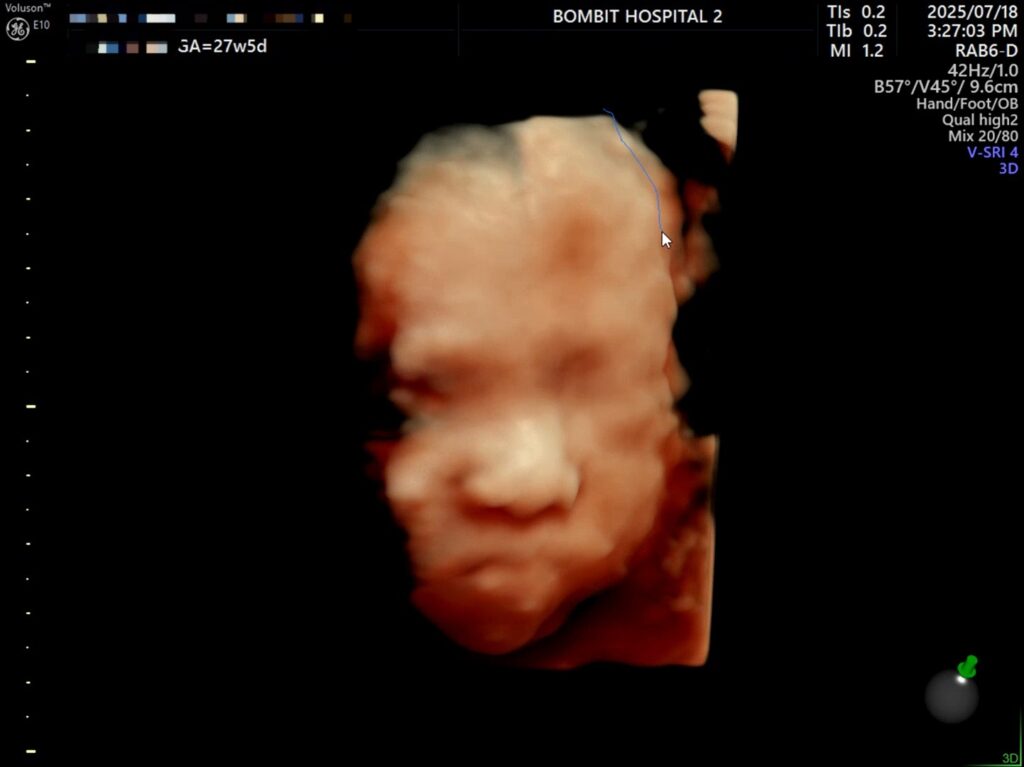

그렇게 다행스럽게도 단비 얼굴을 볼 수 있게 되었다.

체중은 상위 84%, BPD(머리 폭)이 상위 97%다. FL(대퇴골 길이)도 상위 91%..

입초로 본 단비 얼굴은 정말 너무너무 귀여웠다!! 보면서 코가 복코같이 눌려있다고 생각했는데,, 선생님은 아기 콧대가 높다고 했다. 엄마를 닮아서 그런 듯(?)ㅋㅋㅋ